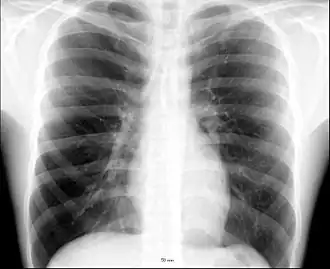

Thoraxfoto, het witte web rondom het hart bestaat uit de vaten uit de longhila

Op een thoraxfoto zijn de longhila altijd goed zichtbaar omdat de bloedvaten er zich sterk aftekenen tegen het omliggende longweefsel. Opgezwollen lymfeklieren rond de longhila (zoals bij sarcoïdose) zijn dan ook altijd goed te zien op thoraxfoto's.